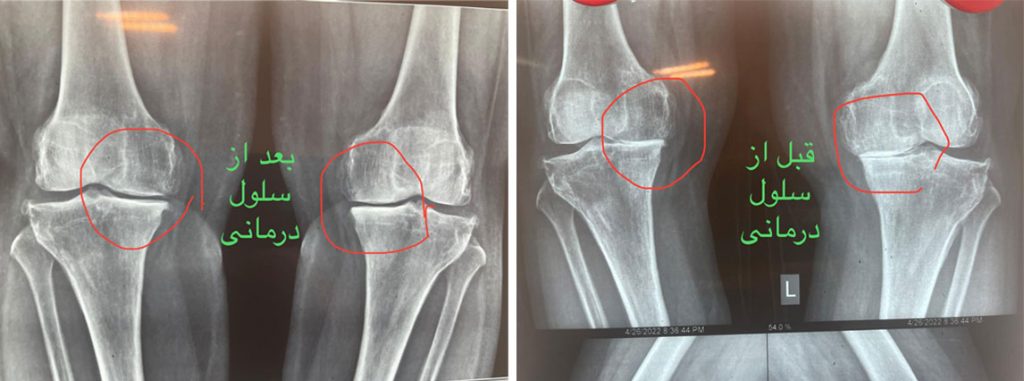

سلول درمانی زانو قبل و بعد